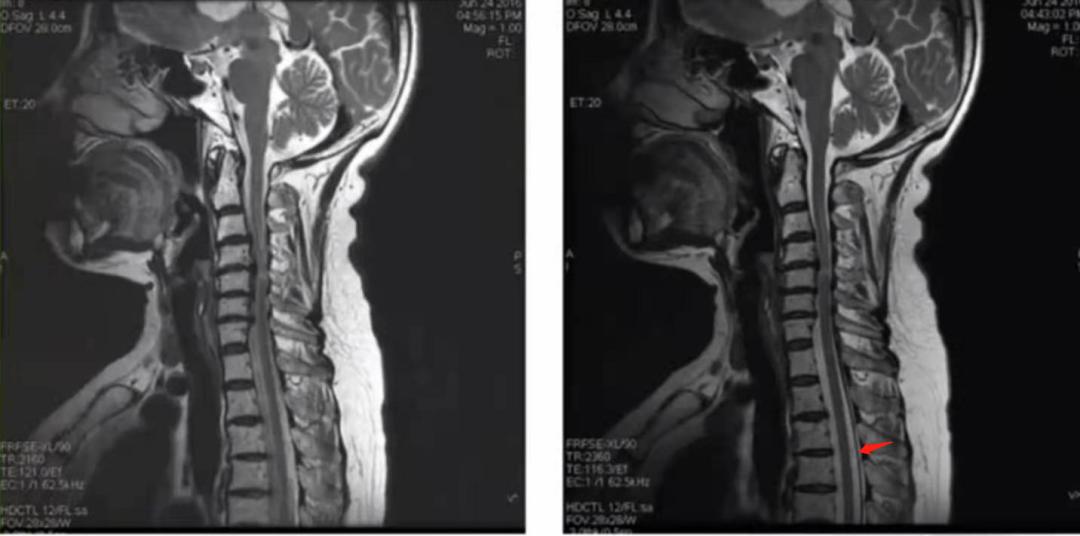

所以说磁共振扫描时,我们把短轴方向设置为相位编码方向时好处多多,那我们是不是在脊柱矢状位扫描过程中也可以这样设置呢?大家感兴趣可以自己试一下。

在这里大家也可以在自己的设备上扫脊柱时做个测试,相位编码设置前后方向,频率编码方向设置上下方向,然后再扫描相位编码设置上下方向,频率编码方向设置前后方向。

因为脑脊液是流动的,在上下方向,需要加流动补偿技术,可以继续测试不同相位编码方向加流动补偿的图像效果。在前面看了北医三院赵强老师的视频之后,有老师留言说流动补偿技术还是不太理解,下面为流动补偿技术内容,内容来源于杨老师的磁共振成像技术指南。

流动补偿的临床应用:FC技术能够减少或消除的主要是沿着施加了FC梯度场方向上的流动液体造成伪影。在SE和GRE中,选择FC后,FC梯度场施加于层面选择、频率编码、相位编码三个方向上;而在FSE序列中,FC一般仅能在层面选择和频率编码这两个方向中选择一个方向施加。临床上,应该把FC方向设置为流体流动的方向,流动补偿才会起作用。另外,FC对于消除层面内流体引起的流动伪影效果较好,而消除垂直于层面的流体造成的流动伪影效果不甚理想。(1)在肝脏成像时, 在T1图像上可以鉴别病灶(较暗)和血栓(亮);(2)减少流动失相位造成的信号丢失,提高MRA的质量;(3)减少脑脊液流动伪影,在颅脑,脊柱成像时提高T2上脑脊液的信号;(4)减少血管流动伪影,特别是增强扫描时作用更为明显,例如在肝脏成像中减小血管搏动伪影。需要指出的是在施加了FC技术后,如SE序列和GRE所能采用的最短TE会不同程度延长,扫描层数也会减少,从而影响采集速度。因此在超快速的梯度回波序列中如Balance-SSFP、CE-MRA中一般不采用FC技术。当在脊柱成像中,频率编码方向和流动补偿方向均设置在前后方向上时,会在上下方向上图像的两端产生模糊,缺失伪影(产生Maxwell伪影);多回波扫描时,使用FC后只能进行双回波成像。